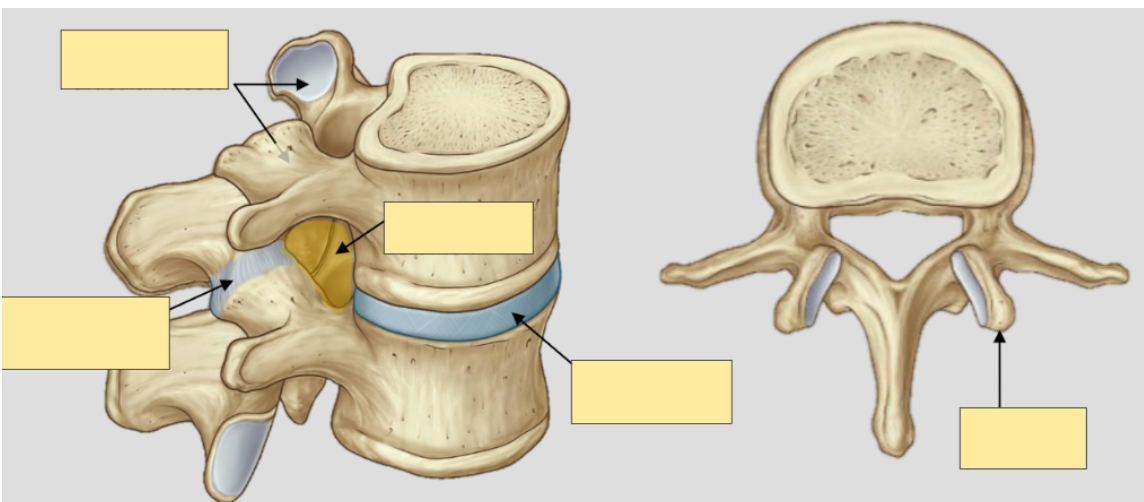

What are intervertebral discs?

What is the function of intervertebral discs?

What is the structure of intervertebral disc?

What is the intervertebral disc a remnant of?

and label

A

• fibrocartilage between vertebrae which provide string attachment between vertebral bodies

• shock absorbers

• outer anulus fibrosus (consisting of type 1 and 2 collagen fibres) and inner nucleus pulposus

• remnant of notocord